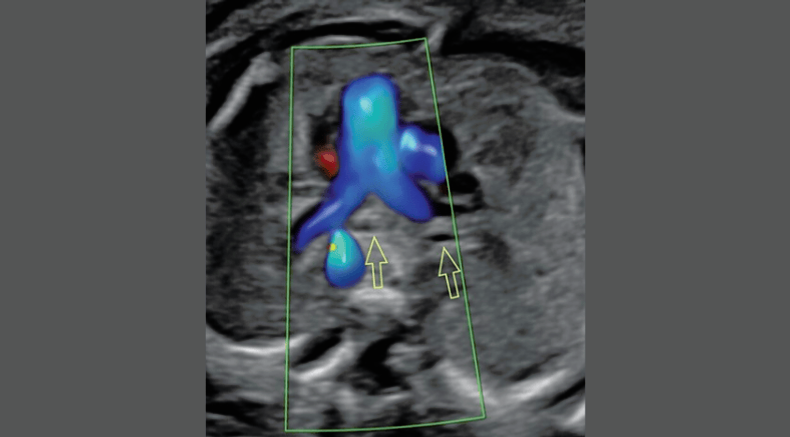

Fetal heart Aortic arch displayed using bidirectional sensitive power Doppler

Chaoui, R. (2021), Evolution of fetal cardiac imaging in 30 years of ISUOG. Ultrasound Obstet Gynecol, 57: 38-42. https://doi.org/10.1002/uog.23551